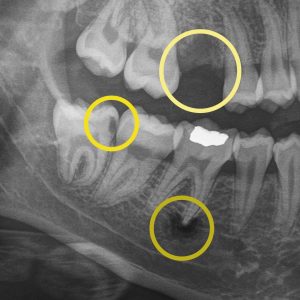

Deep Grooves in Teeth: How Sealants Protect Against Cavities

Dental fissures are deep grooves in the teeth that trap food and bacteria. Learn how sealants protect these areas and